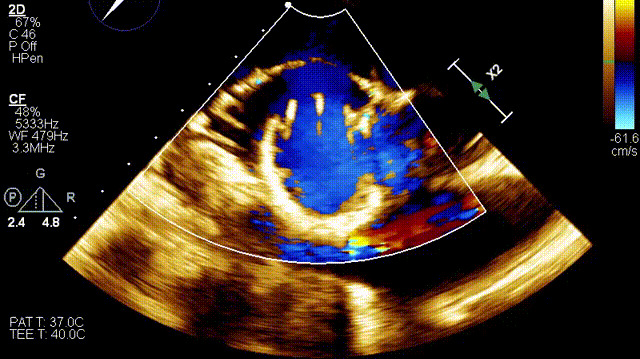

術(shù)后DSA

術(shù)后超聲

在這一研討會(huì)上,廈門(mén)大學(xué)心血管病醫(yī)院王焱教授帶領(lǐng)的結(jié)構(gòu)性心臟病團(tuán)隊(duì),分享了應(yīng)用LuX-Valve Plus經(jīng)血管三尖瓣置換系統(tǒng),為一例超高齡三尖瓣重度反流患者開(kāi)展經(jīng)血管三尖瓣置換手術(shù)。整個(gè)手術(shù)過(guò)程順利,術(shù)后患者三尖瓣反流顯著改善,標(biāo)志著LuX-Valve Plus經(jīng)血管三尖瓣置換系統(tǒng)在福建省的再一次成功實(shí)踐,為三尖瓣介入治療的醫(yī)學(xué)循證添磚加瓦。